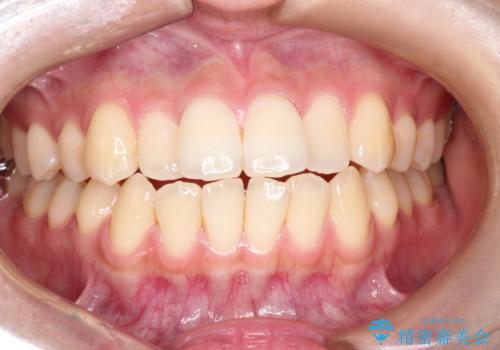

前歯の突出を防ぎながらガタつきを解消。上下左右4番抜歯による審美ワイヤー矯正

担当医 河口智英